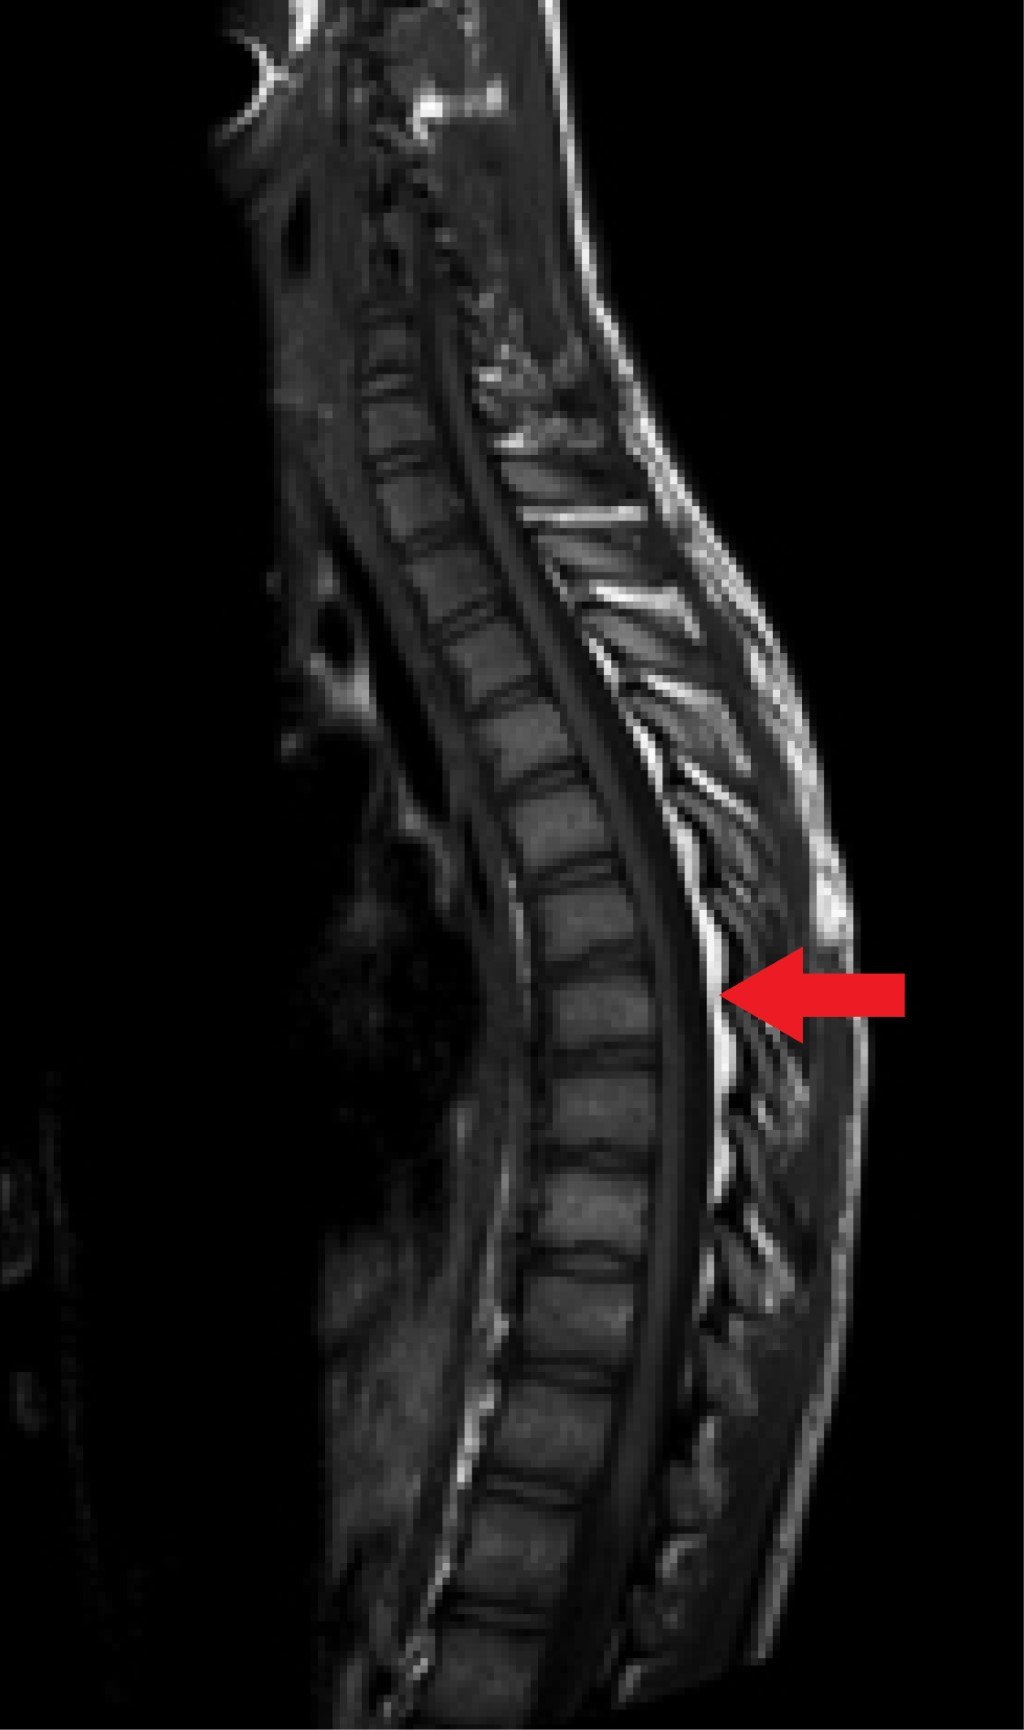

La RM (realizada 20 días después de la segunda consulta) muestra un material hipertenso en las secuencias T1 (Figura 1) y T2 (Figura 2) e hipointenso en la secuencia STIR (Figura 3) en el espacio epidural posterior desde D3 a D9. Con ello se llega al diagnóstico de lipomatosis espinal epidural posterior desde D3 a D9.

El estándar de oro para el diagnóstico de la SEL es la RM ponderada en T1 y las imágenes axiales y sagitales pueden mostrar un aumento de la grasa epidural como una imagen hiperintensa. Las imágenes ponderadas en T2 muestran una intensidad intermedia; la supresión grasa (STIR) es el método de diagnóstico definitivo, mostrando la SEL como una imagen hipointensa.13

Figura 1